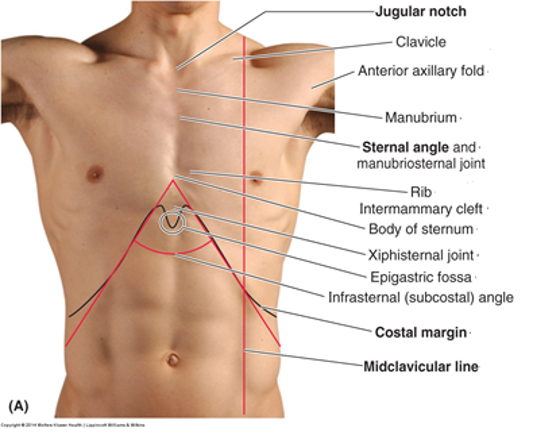

identify:

- Jugular (sternal) notch (JN)

- Sternal angle (SA)

- 2ND rib

- Intercostal spaces (ICS)

- Intercostal spaces 2 - 6

- costal margin (CM)

- subcostal angle (SCA)

name the 2 anterior vertical lines and describe them?

the 2nd one is a little medial to what?

Anterior median (midsternal) line...vertical line through sternum in mid-sagittal plane

Midclavicular lines (MCL)...vertical through midpoints of the clavicles, parallel to median line...medial to the nipple